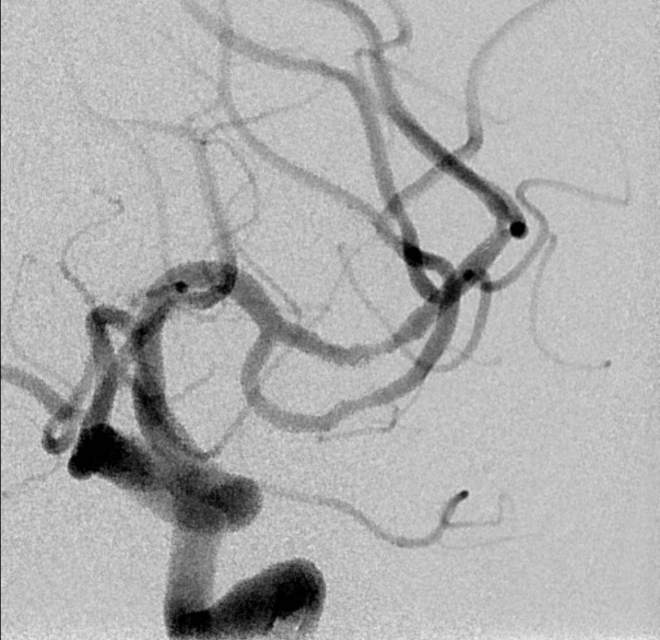

不干预吧,毕竟残存了一些功能障碍,还可能存在再次卒中的风险。通过多学科诊疗(MDT)和脑血管造影(金标准)后,进一步确认了狭窄的存在,左侧大脑中动脉上干血管存在重度狭窄,下干轻度狭窄。手术的难度在于狭窄的部位处于血管弯曲的部位,另外还要为下干预留日后可能干预的空间。

手术顺利完成,狭窄改善,血管直径基本恢复正常。